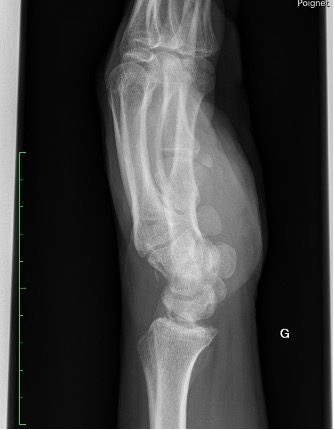

Un patient se présente pour des douleurs au niveau du poignet gauche, suite à une chute à vélo avec réception sur la paume de la main. Cliniquement, nous observons un œdème au niveau du dos de la main, des douleurs à la mobilisation du poignet avec une discrète limitation de l’extension et une prono-supination conservée.

La radiographie effectuée révèle une fracture du triquétrum. Les fractures du triquétrum (ou os pyramidal) sont les fractures du poignet les plus fréquentes après celles du scaphoïde, représentant 13% des fractures des os du carpe. Elles résultent habituellement d’une chute sur la main en hyperextension et déviation ulnaire. Elle est fréquemment retrouvée chez des pratiquant·es de sports de combat.

Il existe trois types de fractures du triquetrum : les fractures corticales dorsales, les fractures du corps et les fractures corticales palmaires. Pour ce patient, il s’agit d’une fracture de type 1 (95% des cas), qui est une fracture par avulsion associée à des lésions des ligaments dorsaux du carpe et considérée comme une « entorse grave du poignet ».

La clinique est aspécifique mais le diagnostic doit être évoqué face à des douleurs sur le côté ulnaire du carpe, après une chute main en extension. Les fractures du triquetrum passent facilement inaperçues sur les radiographies conventionnelles du poignet, mais elles sont souvent associées à des lésions ligamentaires importantes conduisant à une instabilité du carpe, ou évoluent vers une pseudarthrose. Un complément par CT (ou IRM) peut être nécessaire afin de confirmer le diagnostic et préciser les lésions.